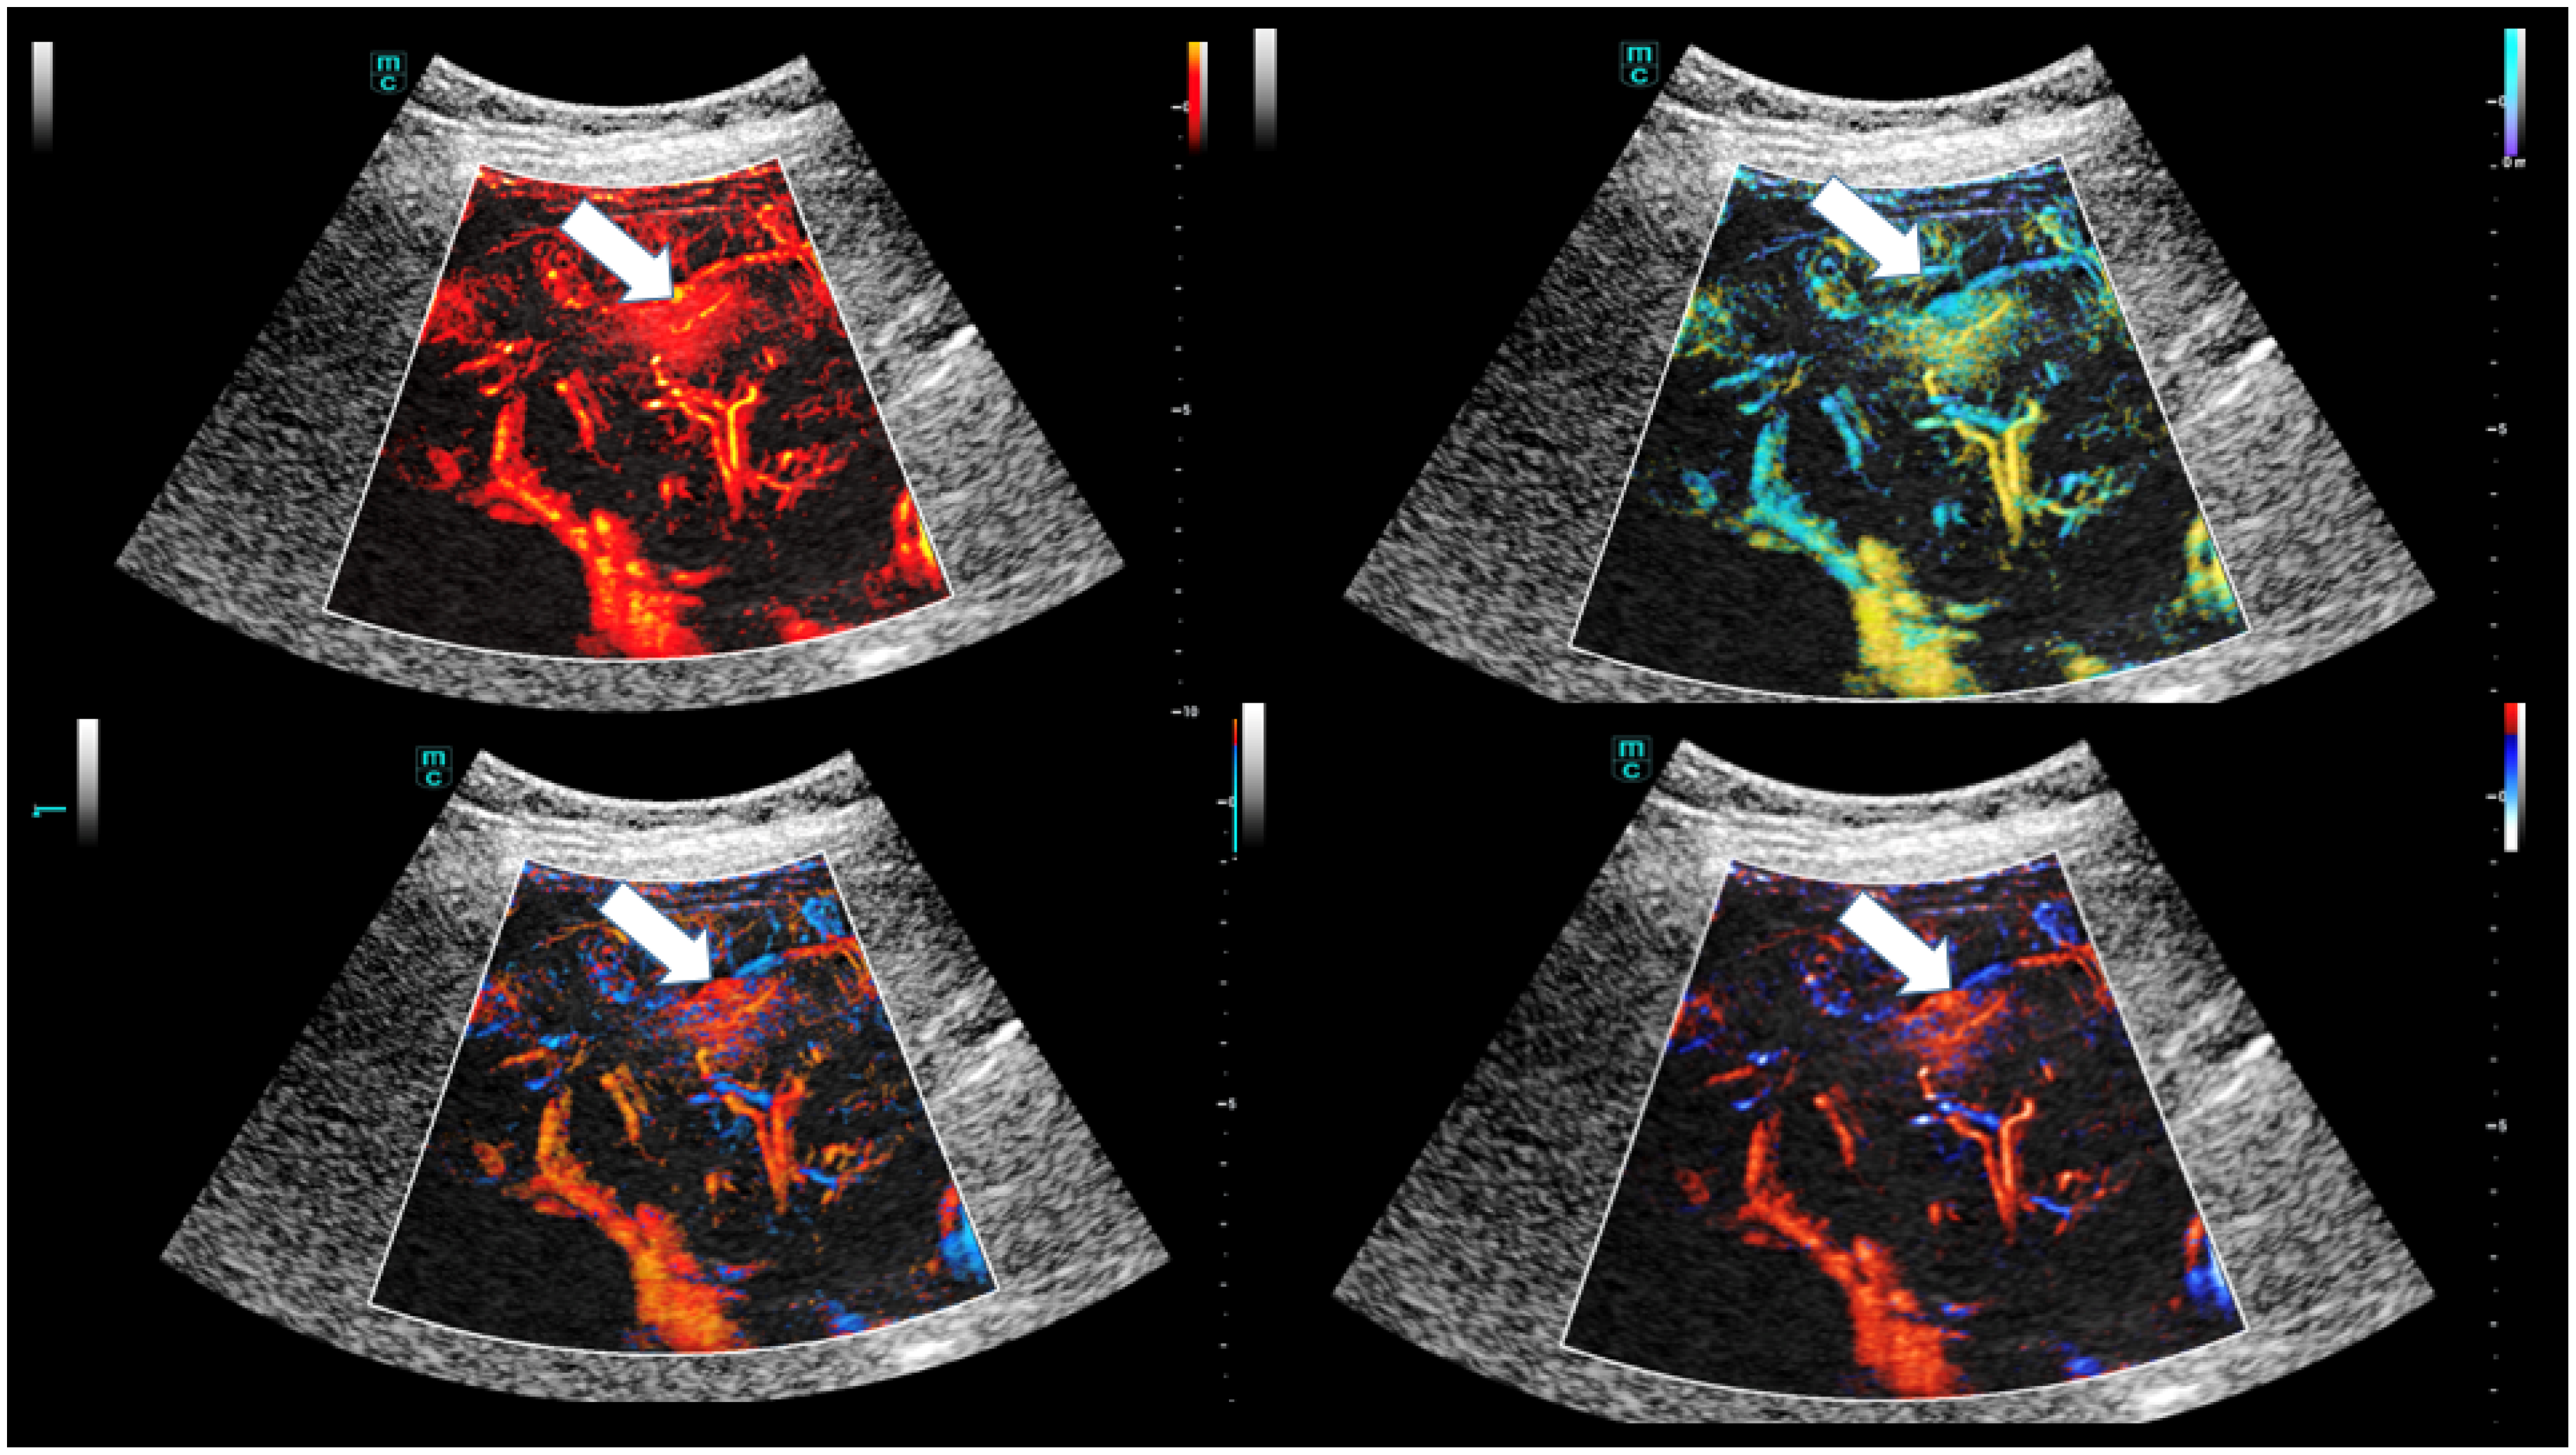

High-Resolution Contrast-Enhanced Ultrasound with SRCEUS for Assessing the Intrahepatic Microvasculature and Shunts in Patients with Hereditary Haemorrhagic Teleangiectasia (Osler’s Disease)

3. Results